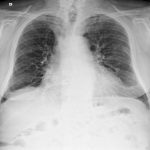

The appropriate position of radiology in COVID-19 diagnosis and treatment—current status and opinion from China

Progress and prospect on imaging diagnosis of COVID-19

Guidelines for the Management COVID-19 Paediatric patient